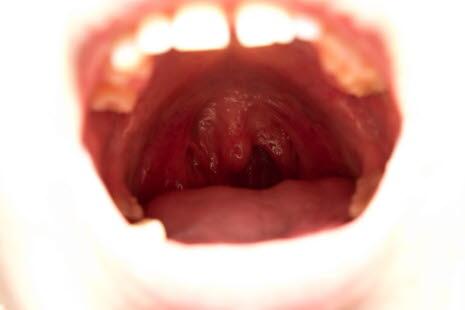

Kreft i munn og svelg - en oversikt

Årlig får i overkant av 600 personer i Norge diagnostisert kreft i munnen og i munndelen av svelget. I 2019 var det 423 menn og 225 kvinner med nyoppdaget kreft i dette området. Munnhulekreft omfatter kreftsykdom i lepper, munn, tunge, gummene og spyttkjertlene. Svelgkreft betyr i denne sammenheng kreft i den delen av halsen som er rett innenfor munnen (orofaryngeal kreft).

Årlig dør knapt 150 personer i Norge av kreft i munnhulen og svelget. Tidlig diagnose medfører at sykdommen i de fleste tilfeller kan behandles med svært godt resultat. Dessverre er det mange krefttilfeller i munn og svelg som oppdages sent, det vil si på et tidspunkt der kreften har vokst inn i annet vev eller har spredd seg til andre deler av kroppen. Dette er fordi kreft i munn og svelg er smertefri i tidlige stadier og fører ikke til legekontakt.